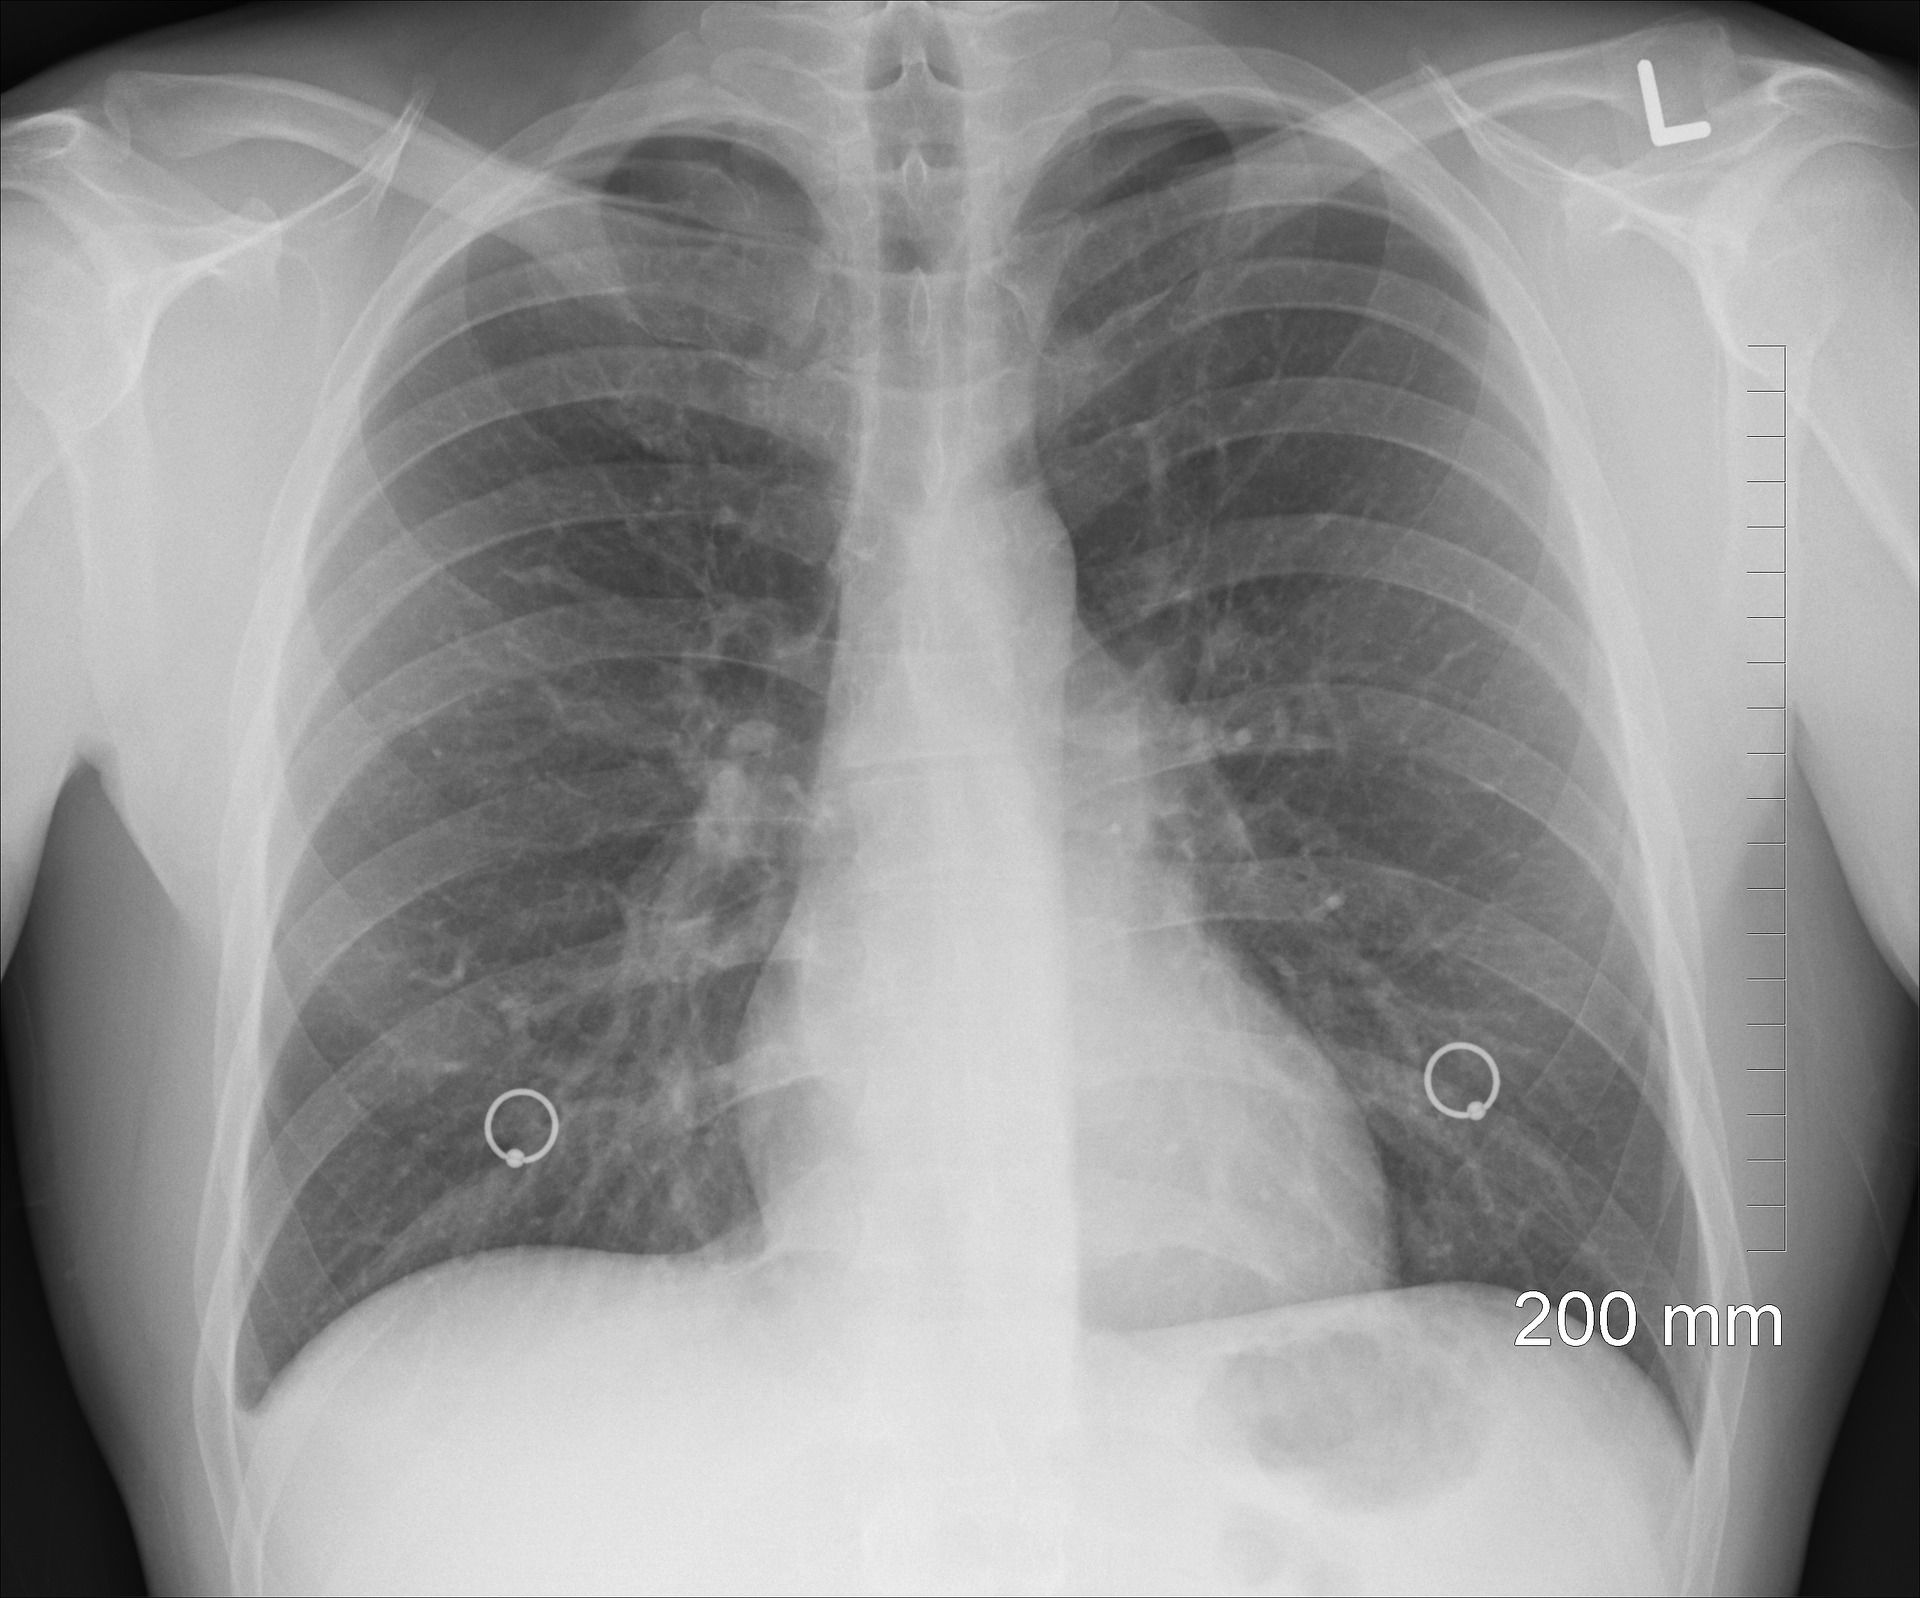

Monotone Tätigkeiten sind für Menschen ermüdend und zeitaufwändig. Die gleichförmige Auswertung von Dutzenden Mammographien durch erfahrene Medizinerinnen und Mediziner kann zum Beispiel den Nebeneffekt haben, dass kleine, aber für die Diagnose wichtige, Details übersehen werden. Der Einsatz von KI kann hier potenziell entlasten und menschliche Entscheidungsträger unterstützen. „Grundvoraussetzung ist, dass die menschlichen Experten dem KI-System vertrauen können müssen. Allerdings kann dies auch dazu führen, dass der Arzt oder die Ärztin die Entscheidung der KI nicht mehr kritisch überprüft“, sagt Prof. Dr. Marc Aubreville. Denn auch solche Systeme, die im medizinischen Bereich bereits zum Einsatz kommen, sind nicht unfehlbar. Deshalb sind in den Abläufen nach wie vor Menschen als letzte Entscheidungsinstanz vorgesehen.